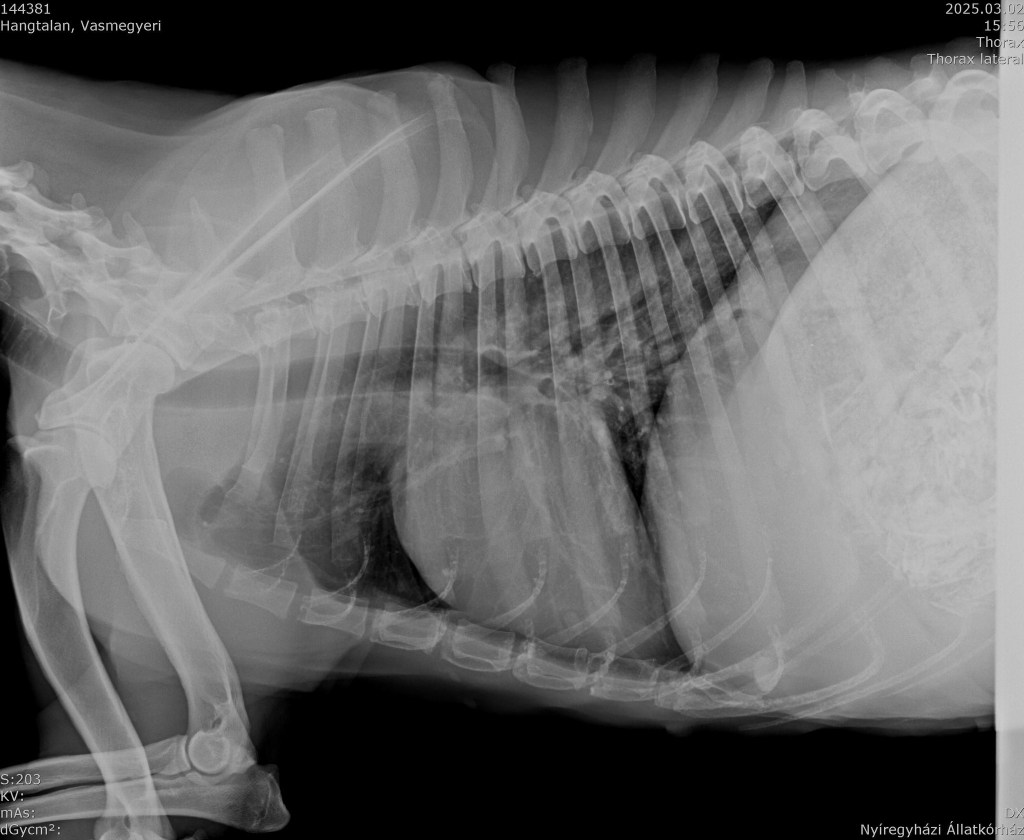

Leider war der Zustand der HĂŒndin bereits zu kritisch und eine OP wĂ€re ohne BeschĂ€digung der anderen Organe nicht mehr möglich gewesen. Sie wurde gehen gelassen… nach einem offenbar langen und schmerzvollen Leidensweg, den ein wirklich tierlieber Besitzer ihr erspart hĂ€tte. Es ist sehr wahrscheinlich, dass sich die HĂŒndin mit ihren letzten KrĂ€ften ĂŒber die StraĂe geschleppt hat und dort liegen blieb, weil sie einfach nicht mehr konnte. Sie war klapperdĂŒrr und muss ĂŒber Monate hinweg sehr gelitten haben. Wir nennen das TierquĂ€lerei und der Mensch, der einst fĂŒr sie verantwortlich war, darf keinesfalls ungestraft davon kommen. Deshalb bittet unser Partnertierheim um vertrauliche Hinweise aus der Ortschaft und hofft so, den Besitzer finden zu können. Der HĂŒndin hilft es nicht mehr. Sie musste von ihrem Leiden erlöst werden. Es ist viel zu traurig und herzzerreiĂend, um verstehen zu können wie ein Mensch das Leid eines Tieres derart ignorieren kann. Es gibt immer Möglichkeiten sich Hilfe zu holen…